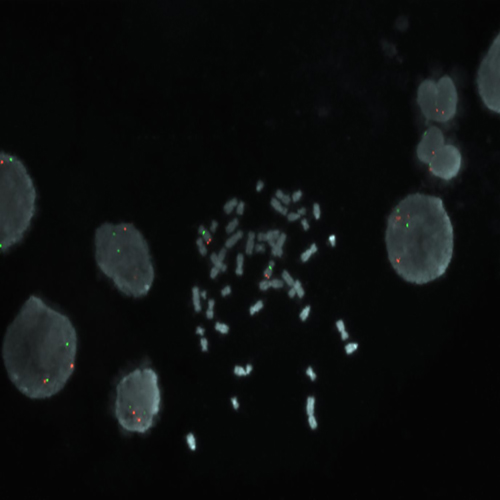

MYC (8q24) / SE 8 hybridized to a metaphase spread showing a normal pattern.

The MYC (previously known as C-MYC) gene produces an oncogenic transcription factor that affects diverse cellular processes involved in cell growth, cell proliferation, apoptosis and cellular metabolism. The MYC oncogene has been shown to be amplified in many types of human cancer such as bladder, breast and cervical. Amplification at 8q24 including MYC is also observed in 5% of CLL patients. MYC is also the prototype for oncogene activation by chromosomal translocation. The MYC (8q24) specific FISH probe is optimized to detect copy numbers of the MYC gene region at 8q24. The chromosome 8 Satellite Enumeration FISH probe (SE 8) at D8Z1 is included to facilitate chromosome identification.